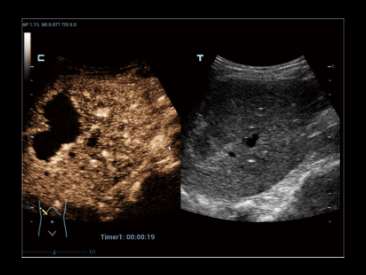

iFusion

Технология совмещения диагностических изображений, разработанная Mindray, с уникальным алгоритмом компенсации изменений, вызванных механикой дыхания. iFusion нового поколения с компенсацией дыхания обеспечивает отличные клинические показатели и превосходную эргономику использования, поддерживает различные ультразвуковые режимы и широкий спектр целевых маркеров для удобной, высокоточной и безопасной навигации. iFusion обеспечивает значительно большую диагностическую уверенность, высокоточную навигацию при интервенционных вмешательствах, а также своевременную и эффективную послеоперационную оценку лечения.